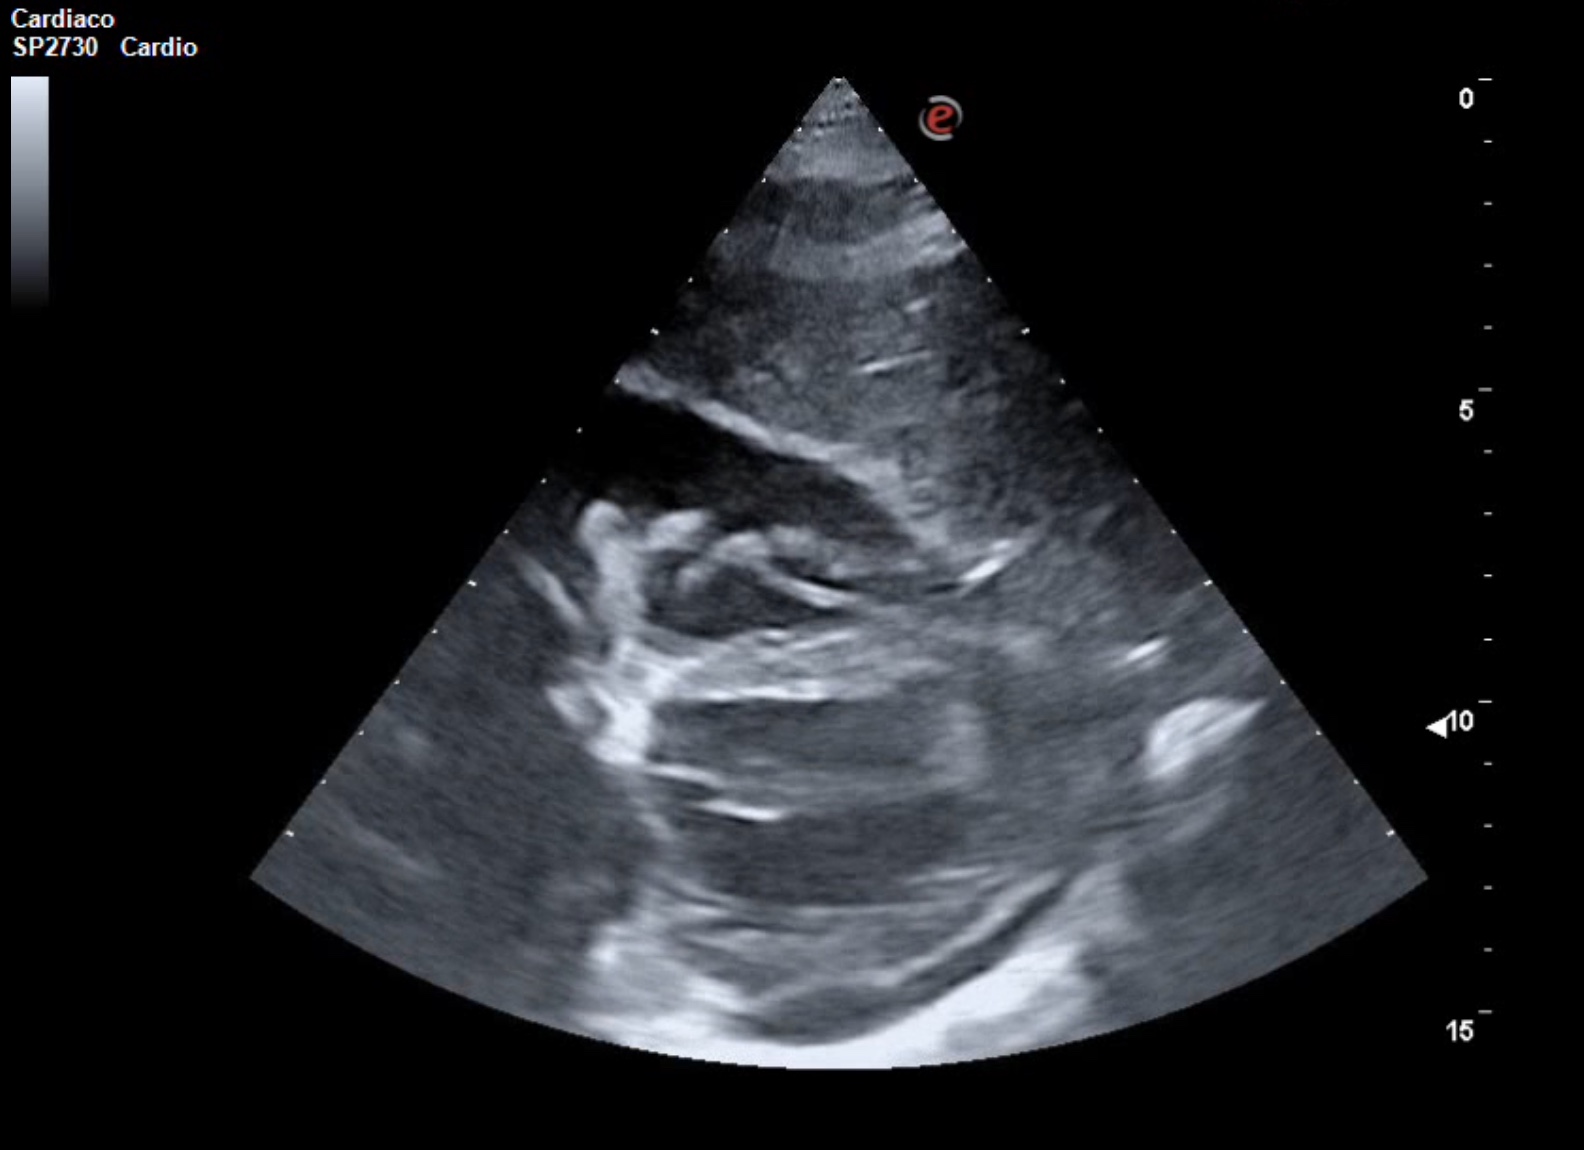

La ecocardioscopia mostró ventrículo izquierdo no dilatado con función sistólica conservada, sin hipertrofia del septo interventricular ni valvulopatías. Aurículas izquierda y cavidades derechas de tamaño normal. TAPSE normal. Se evidenció un derrame pericárdico moderado sin signos de taponamiento cardíaco. Calibre de vena cava inferior normal con colapsabilidad mayor del 50%. Hallazgo de derrame pleural derecho moderado.

La ecografía clínica desempeñó un papel fundamental en la evaluación inicial del paciente, permitiendo una detección rápida y precisa de hallazgos que guiaron la toma de decisiones clínicas. La ecocardioscopia realizada reveló un derrame pericárdico moderado, sin signos de taponamiento cardíaco y un derrame pleural derecho significativo. Estos hallazgos fueron esenciales para descartar la presencia de un cuadro obstructivo que pudiera haber requerido una intervención inmediata. Además, la ecografía permitió valorar el estado hemodinámico de la paciente de forma no invasiva, asegurando que el derrame pericárdico no comprometiera la función cardíaca. En la radiografía de tórax se objetiva una masa mediastínica. La capacidad de detectar y cuantificar de forma precisa tanto el derrame pleural como el pericárdico sin necesidad de esperar a pruebas más complejas, permitió que la paciente fuera ingresada de manera adecuada para un estudio exhaustivo y sin demoras innecesarias.